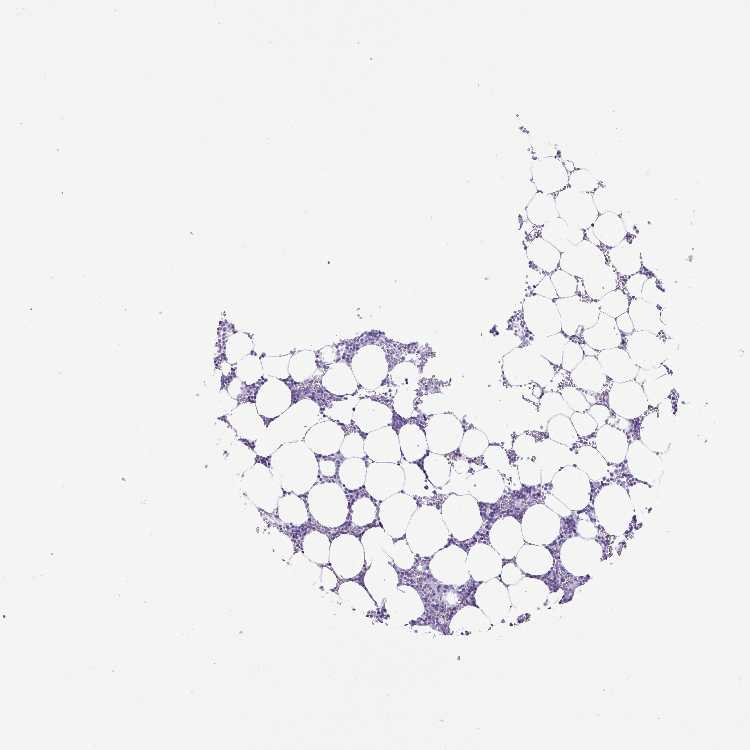

BONE MARROW - Antibody stainingi

Antibody staining in the annotated cell types in the current human tissue is reported as not detected, low, medium, or high, based on conventional immunohistochemistry profiling in selected tissues. This score is based on the combination of the staining intensity and fraction of stained cells.

Each image is clickable and will lead to virtual microscopy that enables deeper exploration of all samples and also displays staining intensity scores, fraction scores and subcellular localization as well as patient and tissue information for each sample.

Antibody HPA051880

Hematopoietic cells Not detected